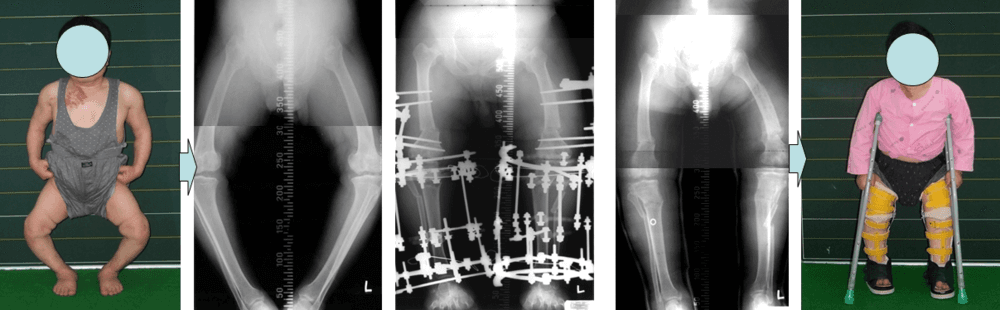

소아마비환자의 하지변형에 대한 교정